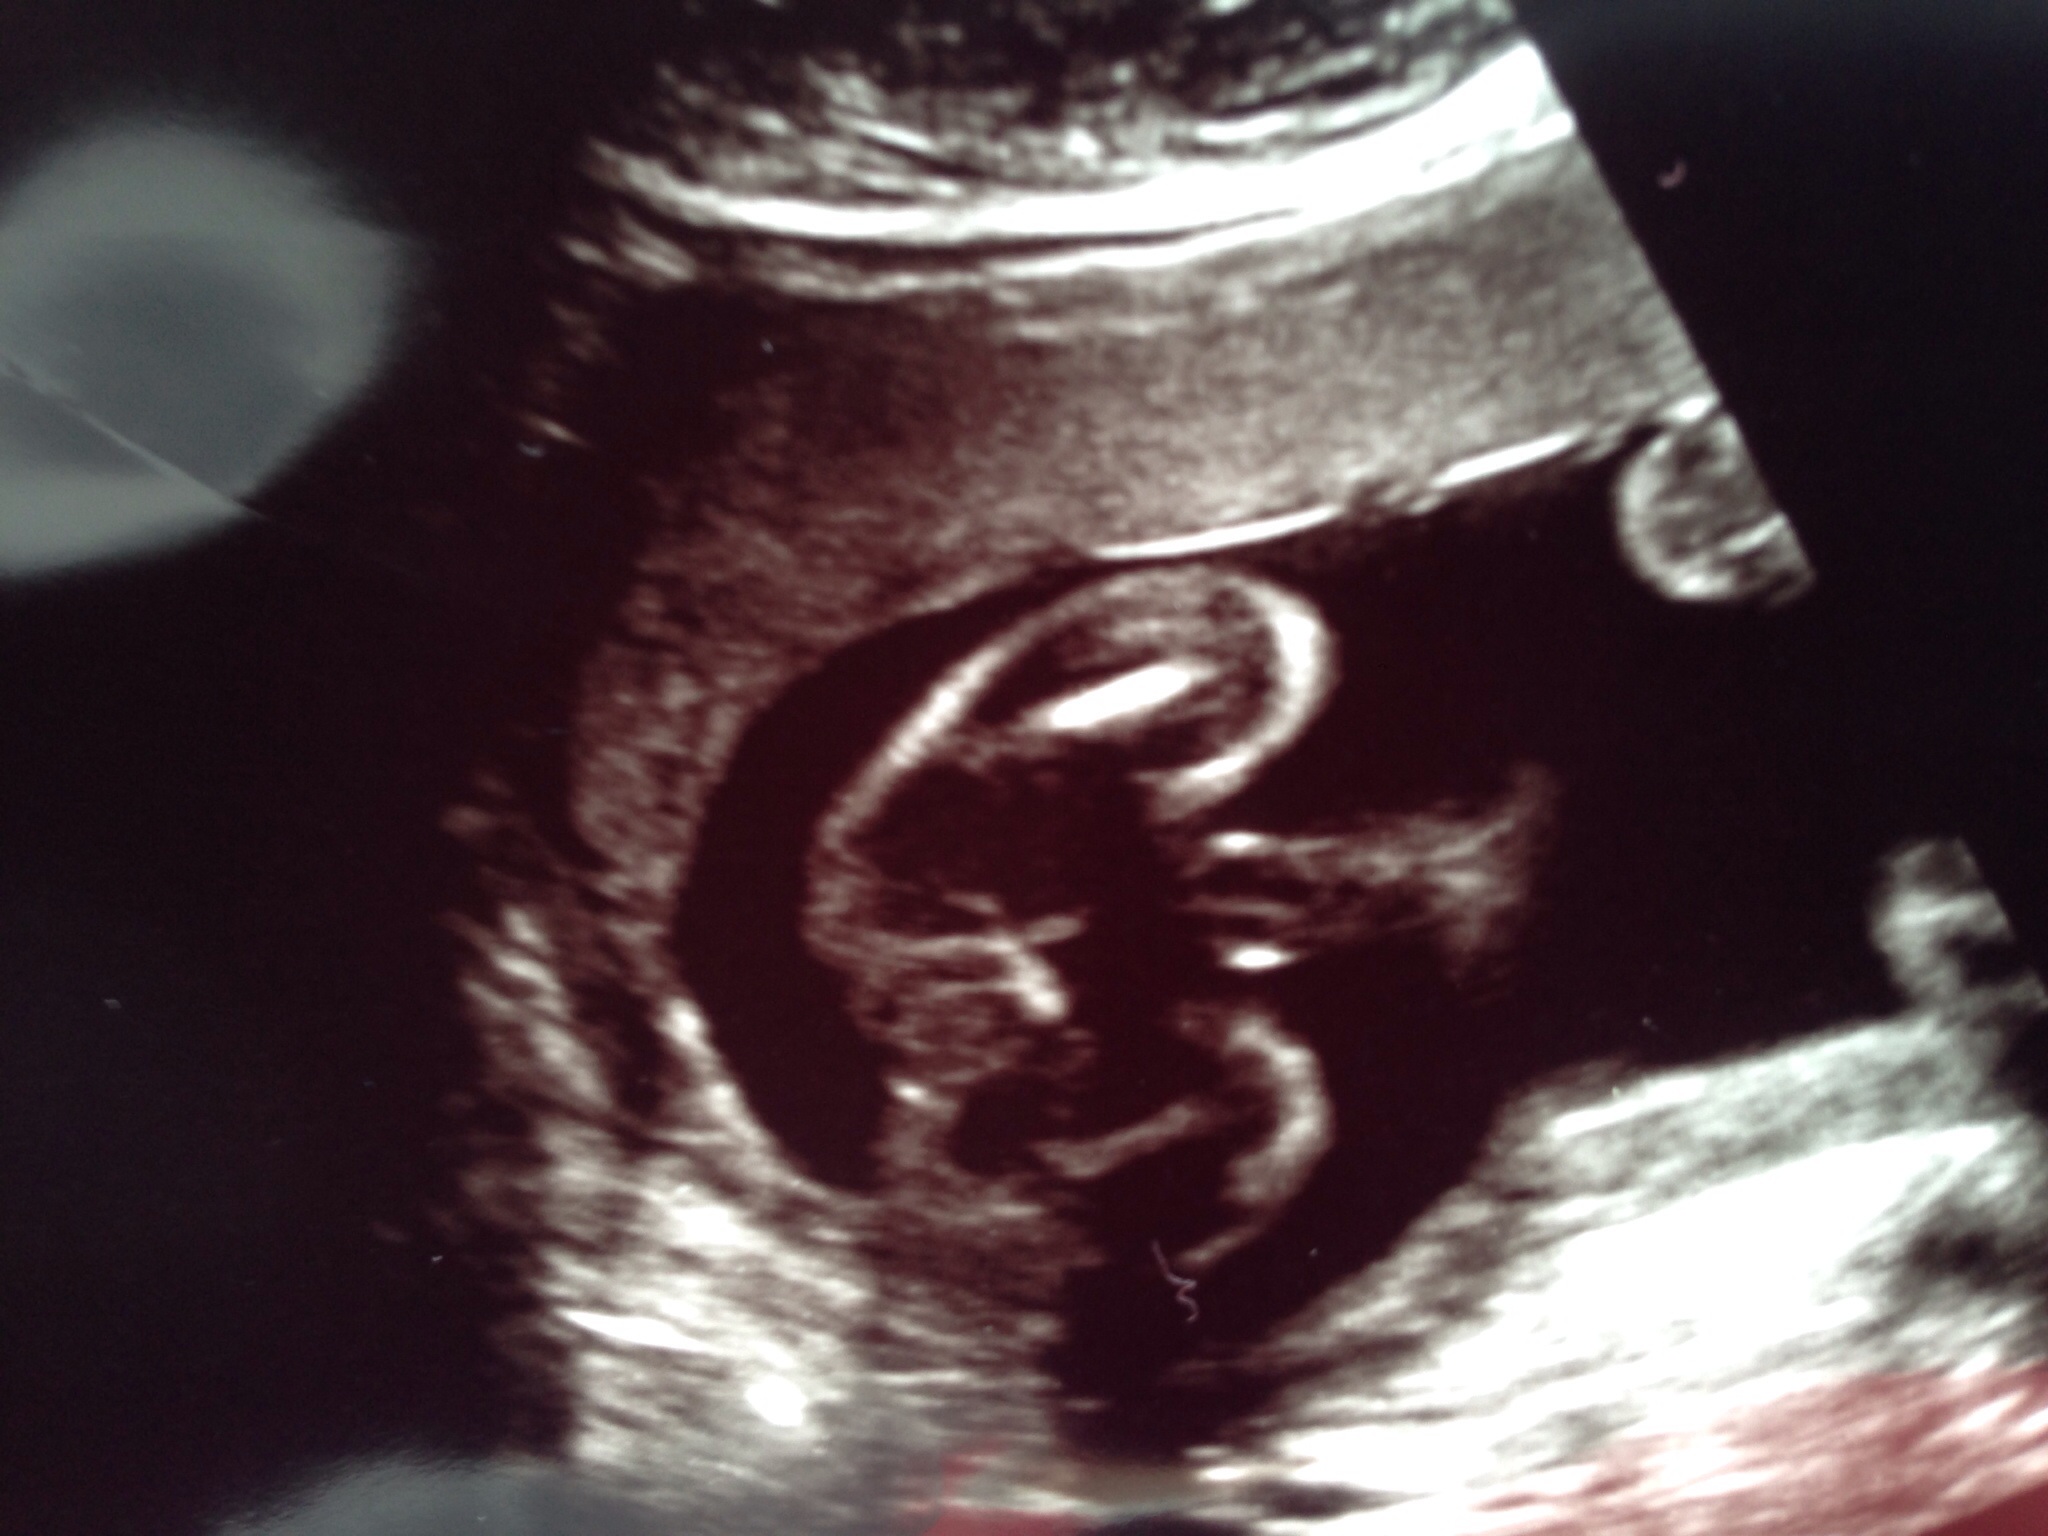

We were told girl and the tech seemed certain about it. Just looking for reassurance!Attachment 24597

Definite girly bits. Congrats!

Girl

Girl.